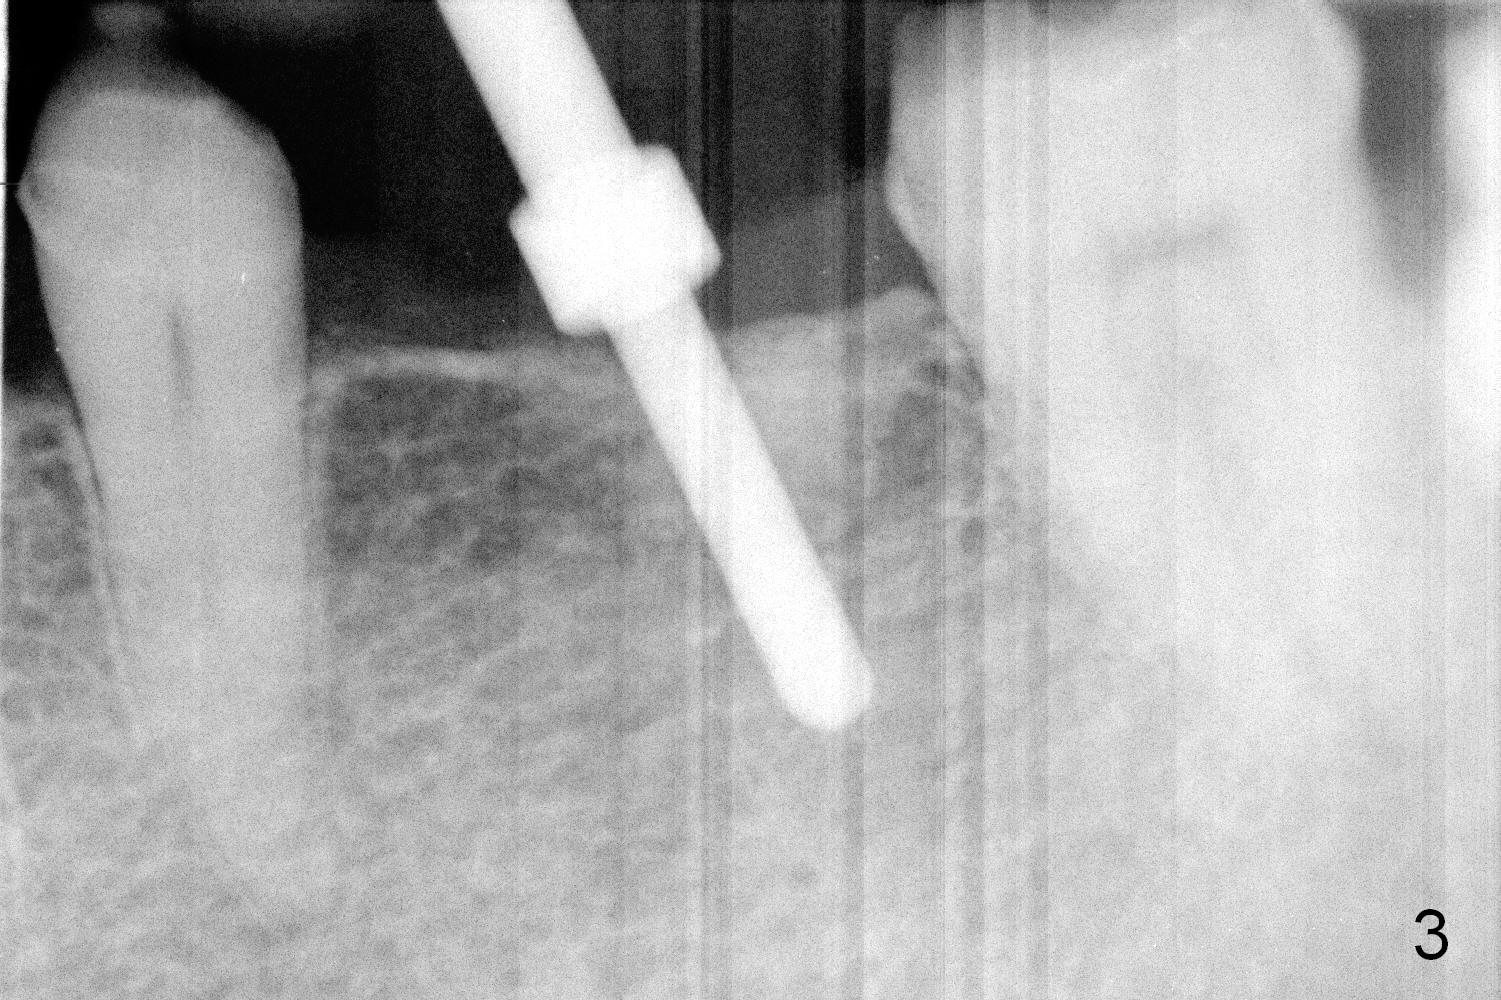

When the patient returns for implant placement, he is pleased to let us know that he has stopped smoking for a week. The edentulous ridge at #19 looks wide (Fig.1). The tooth #3 is supraerupted, while there is no clearance between the abutments (#18 and 20) and the opposing dentition (Fig.2). After incision, the ridge is confirmed to be wide with the aid of implant positioners. The bone is felt soft during initial osteotomy (Fig.3). Attention is being paid to correcting the trajectory. Under prep is ignored. When a 5.9x10 mm implant is placed, the insertion torque is between 25 and 30 Ncm (Fig.4).